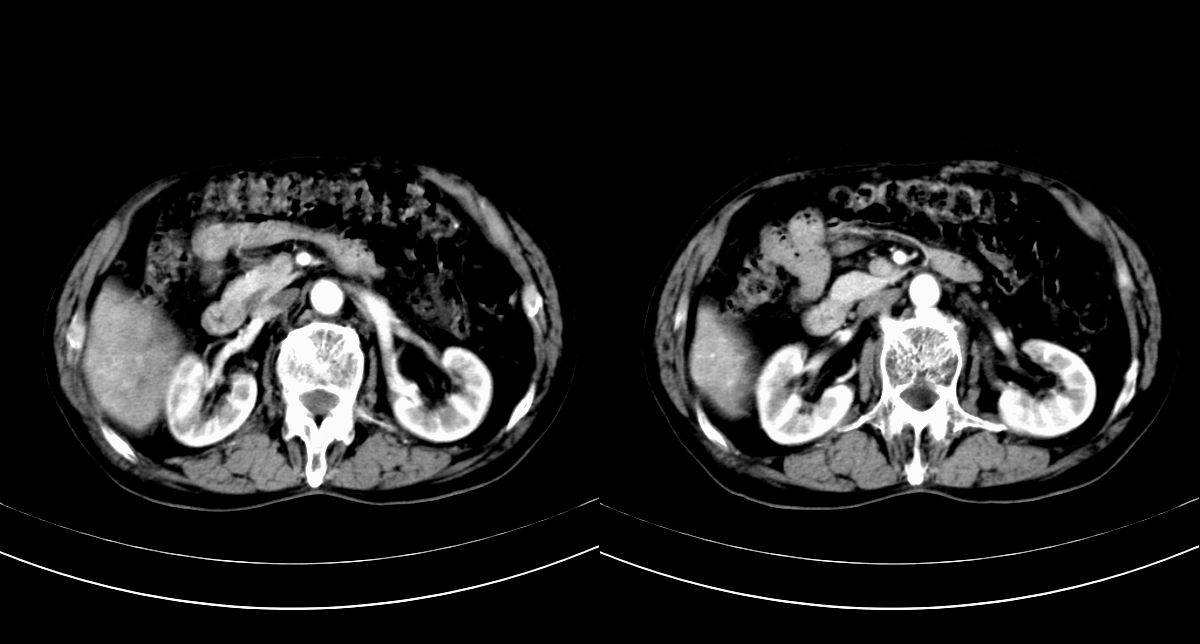

男,79y,无不适。体检发现肝脏占位。

肝内多发低密度结节,增强动脉期明显强化,门脉期逐渐下降,内有液化坏死区。

诊断:

肝细胞癌(结节型)

鉴别:肝转移癌。

肝内多发低密度结节灶,增强动脉期明显不规则环状强化,;门脉期逐渐下降,肿瘤壁厚薄不一,内有坏死液化区。

诊断:肝转移癌可能

鉴别:1原发性肝癌(强化方式符合,建议查afp)

2肝脓肿(无临床病史支持)

诊断:典型的肝转移癌